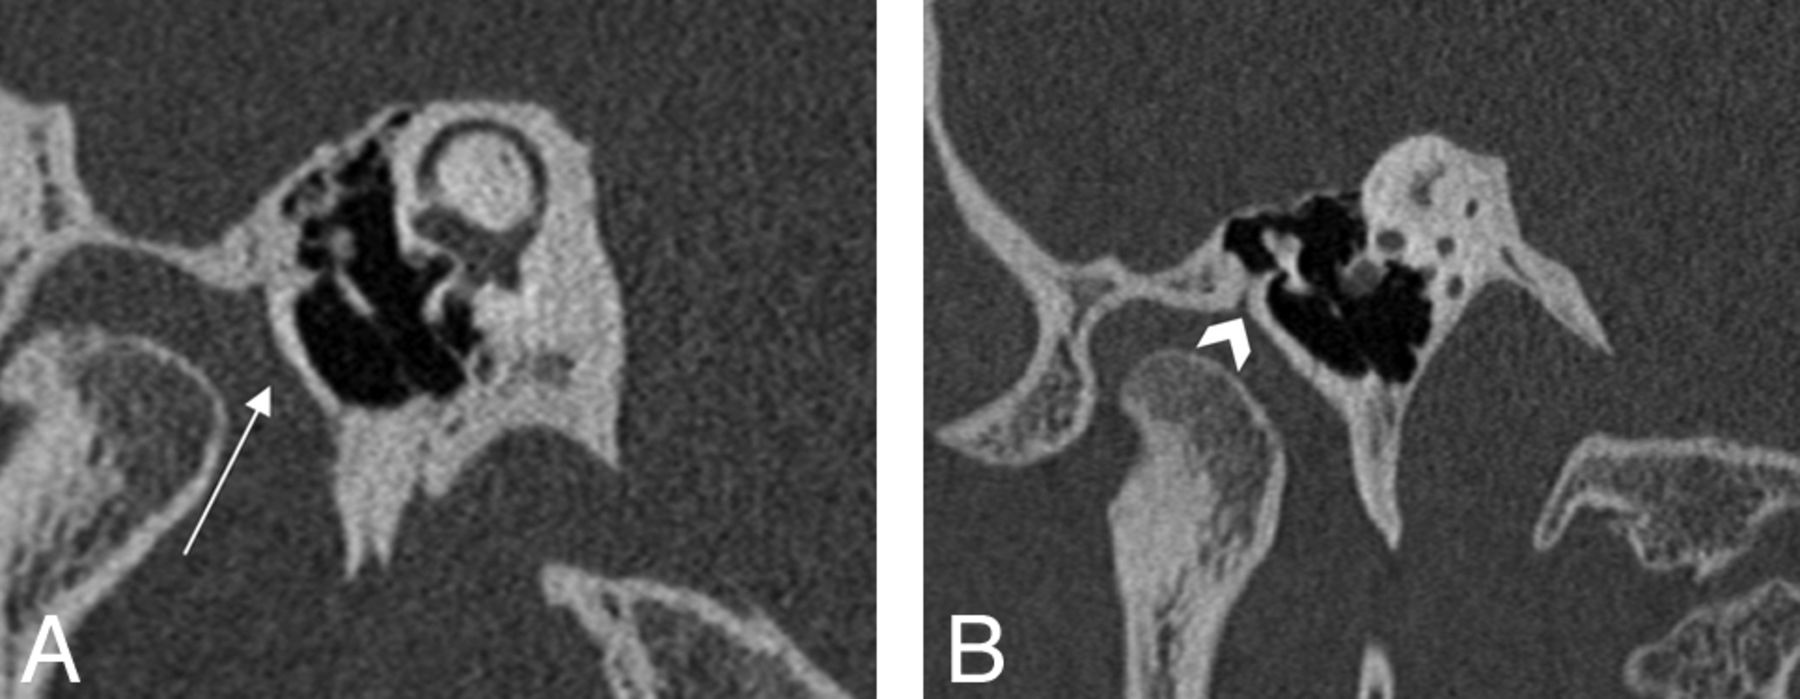

HRCT images with Pöschl views in the same patient demonstrating the tympanic plate (A, white arrow) and the petrotympanic fissure (B, arrowhead).

Cases were assessed for multiple variables. The fracture plane orientation was classified as either transverse, longitudinal, or mixed. These planes were determined relative to the axis of the petrous ridge, with fracture orientations considered longitudinal if <30°, transverse if >70°, or mixed if a combination of both planes was present.4 TPF was confirmed if there was a visible fracture extending through the tympanic plate that was clearly distinct from the petrotympanic fissure (Fig 3B). Fracture extension through the otic capsule was assessed for involvement of the vestibule, semicircular canals, and/or cochlea. The entire course of the facial nerve through the temporal bone was followed for the presence of fracture involvement, including the tympanic and mastoid segments. Facial nerve canal fracture was designated if there was a clear intersection between the course of the fracture and the labyrinthine segment or anterior genu of the facial nerve, while perigeniculate involvement was determined if the fracture line passed within 2 mm of the anterior genu on any planar reformat.

The tympanic part of the temporal bone is a U-shaped structure forming the anterior wall (or posterior margin of the glenoid fossa), floor, and part of the posterior wall of the external auditory canal. The tympanic plate is this anterior wall segment of the tympanic portion of the temporal bone, interposed between the external auditory canal and the glenoid fossa (Fig 1). The plate is subjacent to the squamous part of the temporal bone, from which it is separated by a contiguous set of fissures running along the anterosuperior external auditory canal: the squamotympanic fissure laterally and the petrotympanic fissure medially. The petrotympanic fissure permits passage of the chorda tympani nerve (via the canal of Huguier), fibers from the anterior ligament of the malleus, and the anterior tympanic branch of the internal maxillary artery.25 Identification of this contiguous fissure (best visualized in the Pöschl plane) is important to avoid mistaking it for a temporal bone fracture and in localizing the tympanic plate.